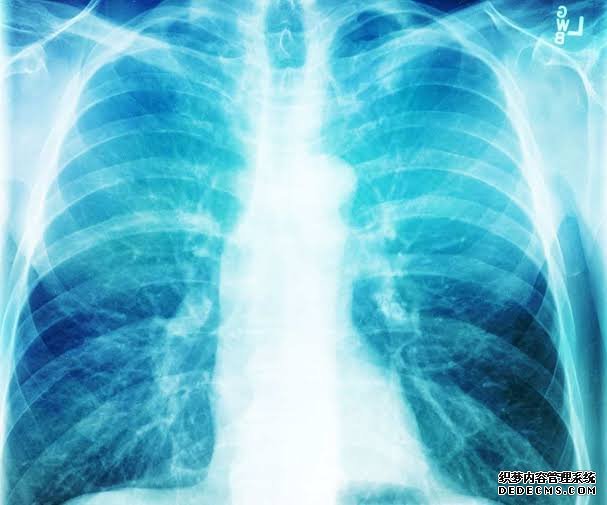

医生进行了多次感染检测,但结果均为阴性。然而,影像学检查显示,这名青少年患有细支气管炎,这意味着肺部最小的气道——细支气管——发炎并阻塞。

根据美国国立卫生研究院(National Institutes of Health)的说法,当时医生怀疑这名青少年可能患有“爆米花肺”,医学上被称为闭塞性细支气管炎,一种罕见的细支气管损伤和发炎的情况,通常是吸入化学物质的结果。

尽管如此,研究人员表示,这名青少年的肺损伤模式与其他与蒸汽有关的肺损伤(也称EVALI)病例不同。医生们说,具体来说,EVALI通常会对肺泡(即肺部的小气囊)造成损害,而在目前的病例中是对细支气管造成损害。